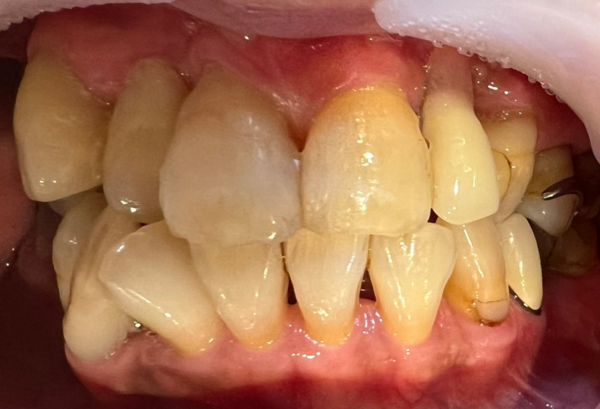

患者様は数ヶ月前に保険適応で入れ歯を作成されたものの、プラスチックが厚いため話しにくく、他の治療方法がないか相談したいとのことで来院されました。また、歯周病で前歯と左上の奥歯を抜いているため、歯周病も合わせて診てほしいとのことでした。

エックス線写真を撮影すると、八重歯が顎の骨の中に埋まっており、左上の奥歯を抜いたところは骨も非常に薄いことがわかりました。このように、埋伏した歯がある場合や、骨が非常に薄い場合、インプラントでの修復は困難であるため、入れ歯での修復が適正であると伝えたところ、違和感の少ない入れ歯での治療を希望されました。

治療後の様子

チタンで作成したことで軽くて薄いので、日々の生活で違和感なく使用できているとのことでした。義歯を作成後、前歯に詰められていたプラスチックも修復しました。